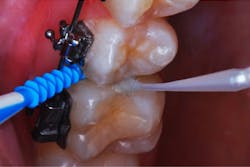

The patient returned for a routine recall appointment on April 6, 2021, wearing fixed orthodontic hardware. A bitewing radiograph was taken (figure 2, top right). The site was cleared with floss, and a new pick soaked with SDF was inserted (figure 3). A small applicator was used to paint sluiceways to enhance the flow of SDF. The pick was slid in and out of the interproximal surfaces a few times (figure 4). The treatment site was immersed in 5% fluoride varnish (figure 5).